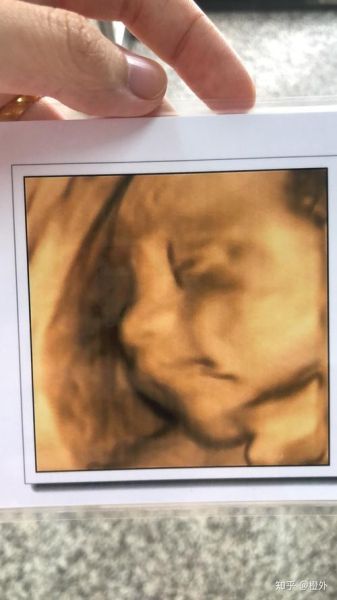

来自广州的林女士在22周大排畸被告知“双侧鼻骨未显示”,夫妇俩彻夜难眠。经过羊水穿刺+基因芯片,结果提示胎儿染色体正常。抱着忐忑,她坚持妊娠,39周顺产一名3.2 kg女婴,**出生后鼻梁略低但呼吸通畅,6个月随访时鼻骨已可见骨化**。 她把孕期B超照片与出生照对比,发现**宫内软组织塌陷让鼻梁“隐形”,生后脂肪垫增厚,轮廓自然显现**。